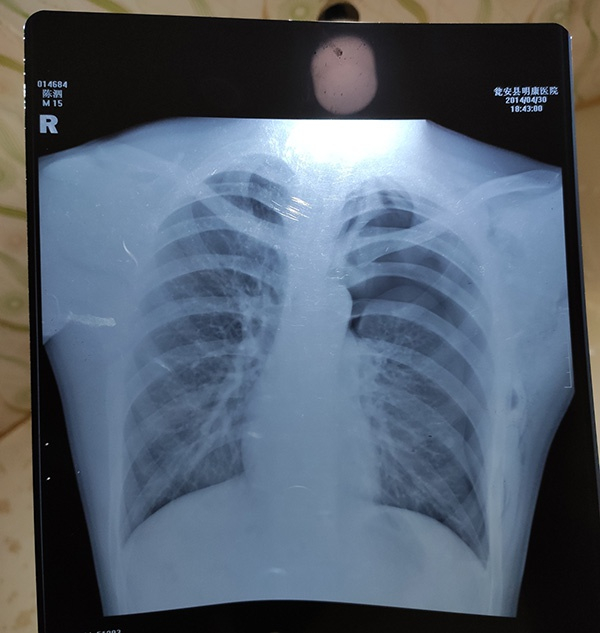

赶到时手术已结束,人还在昏迷中,医生下了病危通知书。当晚的胸片报告显示左肺被压缩约75%,经县公安局法医鉴定为重伤二级。

案发当晚,陈泗翰的胸片。

案发当晚,医院下了病危通知书。